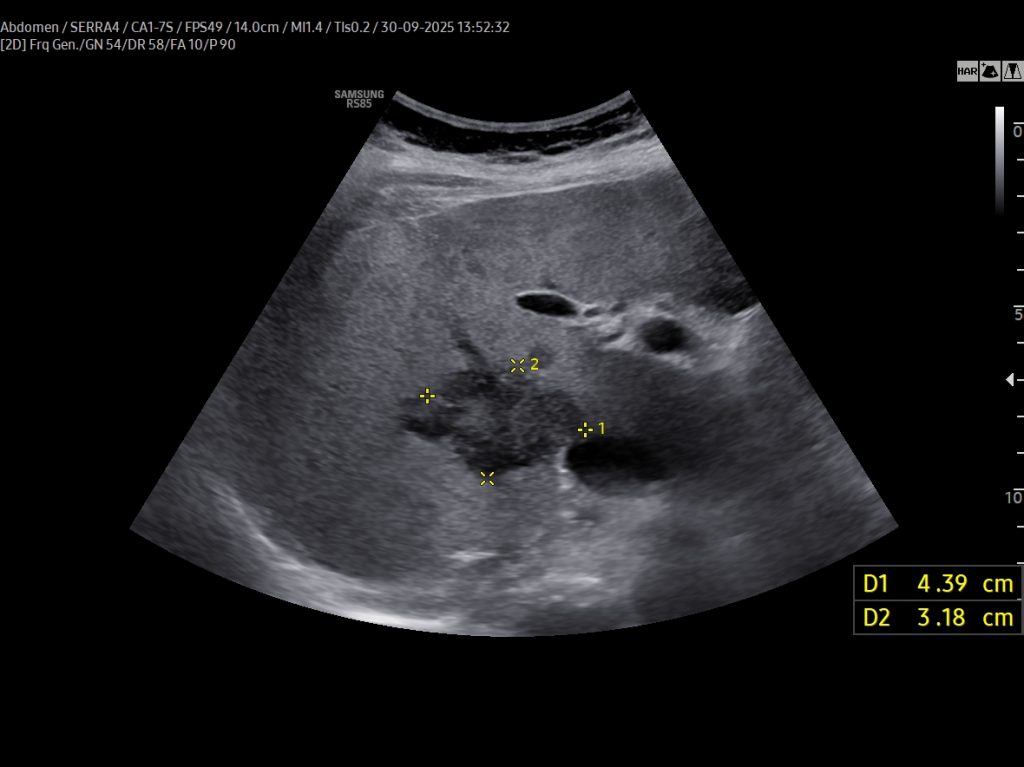

VIDEO 1: On CEUS (Video 1), the lesion exhibited early peripheral rim-like enhancement in the arterial phase, followed by centripetal filling with persistent non-enhancing central areas, likely representing necrotic foci. Washout occurred within one minute, suggesting a cholangiocarcinoma component, either alone or in combination with a hepatocellular component.

On CEUS (Video 1), the lesion exhibited early peripheral rim-like enhancement in the arterial phase, followed by centripetal filling with persistent non-enhancing central areas, likely representing necrotic foci. Washout occurred within one minute, suggesting a cholangiocarcinoma component, either alone or in combination with a hepatocellular component.